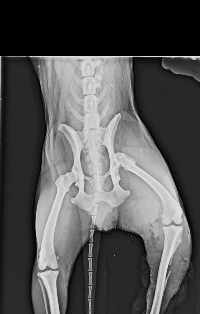

Oi! Estou aqui pedindo a ajuda de vocês para salvar meu cachorro 🐕 ele é um cachorro muito dócil,mas ele acabou se soltando e fugiu para ir atrás de uma cadela no "cio" e acabou sendo atacado por um Pit Bull,levei ele no bem estar animal foi atendido,receitaram remédio e antibiótico para dor e etc,foi feito um raio-x e nesse raio-x constou lesões deslocamento de osso e fratura,vai ser preciso fazer uma cirurgia e a cirurgia custa em torno de 5 mil e mais os gastos dos remédios e a recuperação, não tenho condições de fazer.

Foi passado para mim que no bem estar animal não faz esse tipo de cirurgia,pois eles me encaminharam para um cirurgião ortopédico que vai me ligar para marcar uma cirurgia que não tem nem previsão pois tem outros animais em espera na frente dele.estou aqui pedindo socorro para salvar meu cachorro 🐕.peço a ajuda de todos de coração.🙏🏻